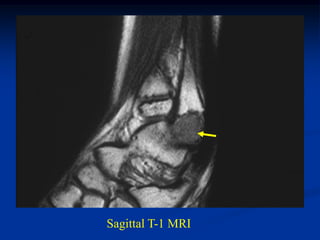

Case #617

26 year male with osteochondroma proximal fibula

Lateral view